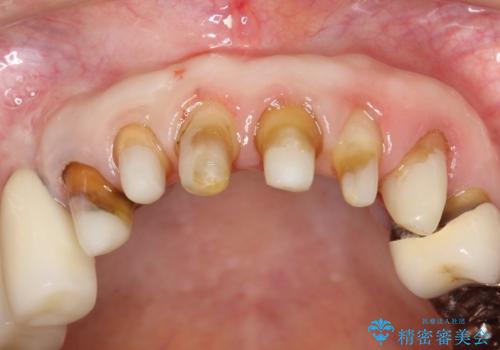

前歯の低クオリティな治療の実態 妥協無い治療で根本からやり治す

・虫歯がとりきれていない

・接触部分がガタガタで適合の悪い金属

・全く無菌の努力がされていない根管治療

など、いい加減な治療は「治療」ではなく、むしろ医原性に歯の寿命を短くします。

最もよくないのは、クオリティの低い治療を何度も繰り返すことです。